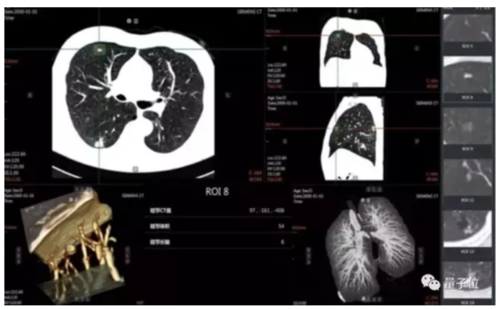

与此同时,这也强化了影像数据的积累和分析,也让基于 AI 的医疗影像分析 应用日趋走向成熟,一个过去需要10分钟进行筛查的肺癌前期诊断,在AI的加持下能够达到秒级,而且准确率也在95%以上。

目前,在医疗影像 AI 分析应用中,目标侦测神经网络正被广泛地运用,其通过深度学习的方法,能够对 X 光片、CT 成像等医疗影像进行高效、准确的病灶检测。

典型的目标侦测神经网络有 R-CNN、Fast R-CNN、SPP-NET、R-FCN 等。R-FCN 是 近年来在医疗影像分析领域常见的目标侦测神经网络模型,其典型的结构入下图所示:

关键所在,是如何让云+AI更好的结合起来,实现无缝的协同,更强大的AI病情分析,也需要对主流的AI框架进行优化升级。

实战手册中,在与西安盈谷 Cloud IDT 智能应用、医学影像处理及分析云计算@iMAGES 核心引擎等相结合后,在肺结节诊断等一大批关键场景中建立起“AI+Cloud”的智能辅助诊断系统能力。